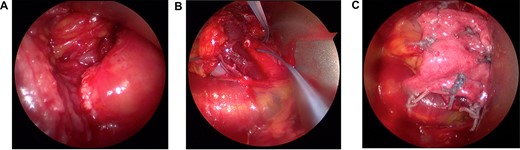

Diagnostic arthroscopy demonstrated a retracted IS tear at the MTJ region (Fig. 3A). The tear site was tagged with a suture arthroscopically for the ease of identification via a posterior open approach (Fig. 3B). After arthroscopy, a 6-cm skin incision starting from the posterolateral corner of the acromion towards the axilla was made. Deltoid split was performed along the posterior raphe to expose the underlying IS muscle and tendon. The MTJ tear was easily identified by the marking sutures placed arthroscopically. High strength, nonresorbable sutures (#2 Fiberwire; Arthrex Inc, Naples, FL) were passed through the tendon and muscle stump in a Mason–Allen configuration across the tear. A patch of dermal allograft matrix (Arthrex Inc, Naples, FL) was placed over the repair, anchored to the tendon and muscle side with interrupted sutures (Fig. 3C). Passive intraoperative shoulder motion demonstrated the IS muscle–tendon unit to move as a single unit.

The infraspinatus tear at the myotendinous junction was identified arthroscopically (A) and tagged with a suture to ease identification during open repair (B). Following muscle to tendon repair across the tear in a Mason–Allen configuration, the repair was reinforced with a dermal allograft patch incorporated over the tear (C).